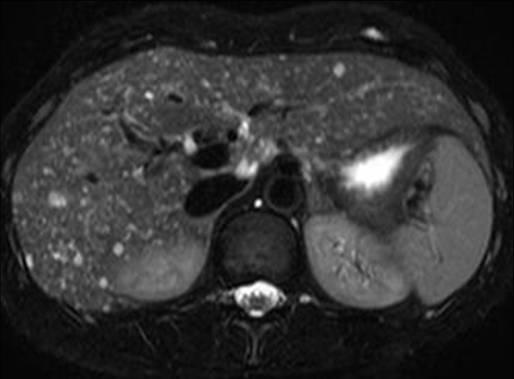

Hamartoma đường mật

» Thông tin: Nam giới – 34 tuổi.

» Lâm sàng: Kiểm tra sức khỏe.